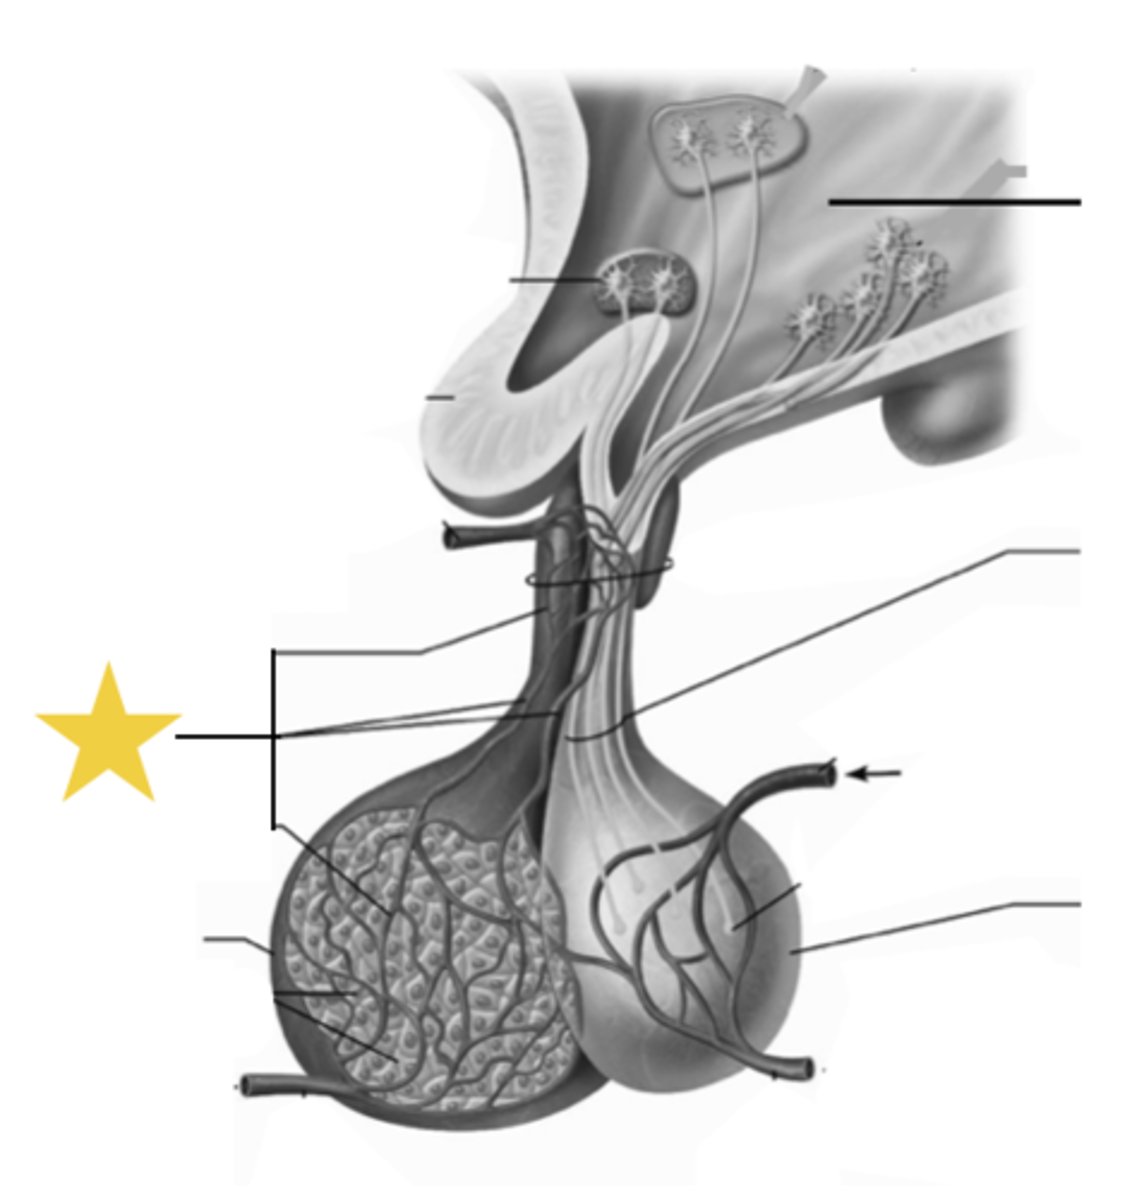

anterior pituitary

ID dark-stained tissue

posterior pituitary

ID light-stained tissue

pars distalis

what part of anterior pituitary?

chromophils (acidophils/basophils) & chromophobes

what cells compose the pars distalis?

pars intermedia

What part of the pituitary:

-posterior portion of the anterior pituitary

-in contact with neural tissue

-most active during fetal development

basophils, chromophobes, and colloid filled cysts (remnants of embryonic hypophyseal pouch)

components of pars intermedia

pars nervosa

made up of modified glial cells and axons that have descended from the hypothalamus